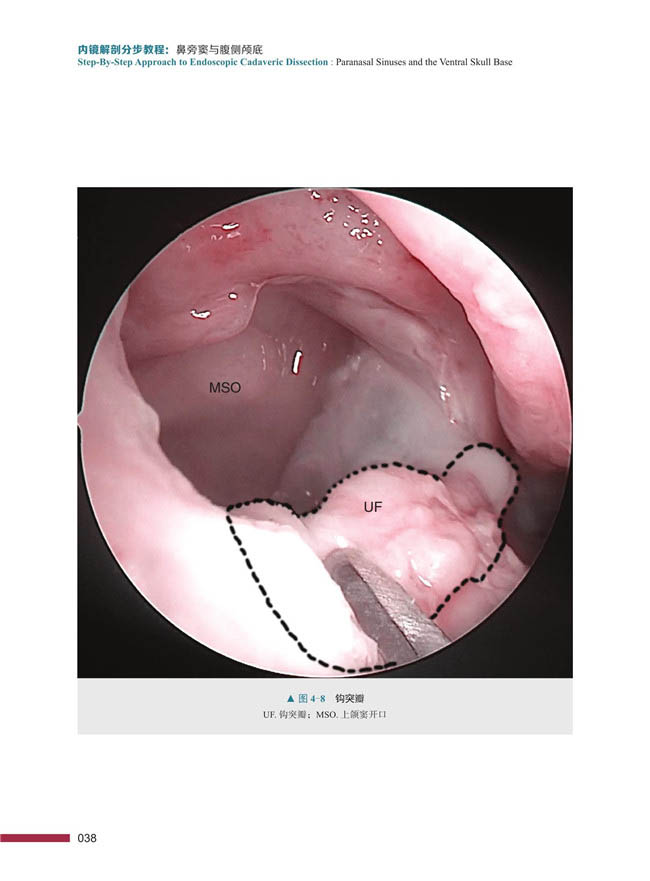

图文并茂 社9787504686923 正版 中国科学技术出版 贾纳基拉姆等著 纳拉亚南 内容新颖独特 鼻旁窦与腹侧颅底 内镜解剖分步教程 包邮